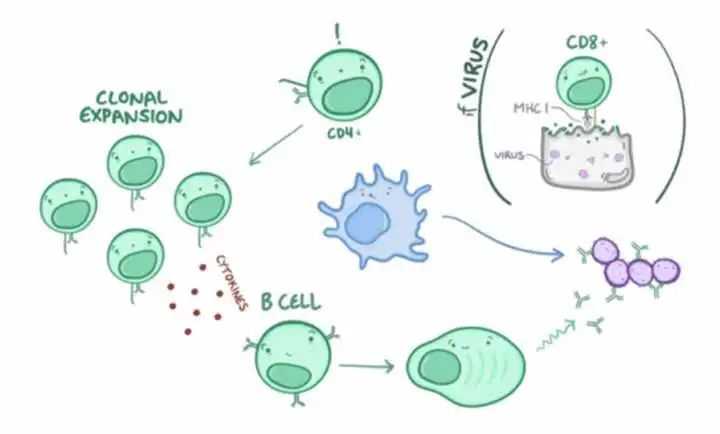

为了和各种病毒细菌共存,为了抵御外来化学毒物和内在炎症对身体的损伤,我们离不开身体的免疫系统。如果身体是一座城池,那么构成免疫系统就是一座军事基地,免疫器官是弹药库、淋巴管淋巴结是堡垒、免疫细胞是战士、免疫分子(抗体补体)是兵器。它们各司其职,配合协作,从发现外来威胁,到发动打击,最终收拾战场并将罪犯记录在案,整个过程用时不超过10天!

对于有害的病毒、细菌和化学物质,我们的免疫系统会首先启动「先天免疫反应」,通过发烧、流涕、呕吐、腹泻等各种方式,杀灭并排出致病物质。这种大规模的杀伤虽然速度快,但对于未知的病原体就没有效果。这时候,我们的身体会启动「获得性免疫反应」,针对敌人的特点研发特效武器,虽然这个过程会花费几周的时间,但一旦研发成功,就会形成“免疫记忆”。

左边:先天免疫大家族;右边:后天免疫大家族

再拿打的流感疫苗来说,往身体里注射了灭活的流感病毒,我们的固有免疫系统当然是无法识别他,通过发烧也消灭不了它,病毒还是存在于血液和淋巴液里,于是淋巴结里的巨噬细胞和血液里的单核细胞就要想办法搬救兵了,那就是免疫细胞的三大将——T细胞、B细胞、NK细胞。

从左到右:NK细胞、B细胞、T细胞

T细胞就像医院门口检查健康码的保安大叔,面对汹涌的排队大军,它要做到忙而不乱,快速独立判断对方是敌是友,毕竟很多人拿着健康码截屏都能混入,病毒细菌有时候更加狡猾,只有经过长时间艰苦的训练,T细胞才能独当一面。

B细胞就像奇门遁甲的忍者,当遇到无法杀灭的病毒时,它们会第一时间使出“影分身”,分裂出大量B细胞一起制造数以万计的抗体,就像手里剑一样往病毒身上发射,杀死病毒的同时,也研发出了可用于对付他们的“专门武器”,未来一旦不幸再次感染,这条生产线就会快速响应,把病毒扼杀在摇篮里。

NK细胞(自然杀伤细胞)就像个毫无感情的杀手,它可以快速标记非自身细胞,只要发现病毒或者肿瘤细胞不是自身的,就二话不说把它们杀灭。但冲动的性格,也让它们时常“好心办坏事”,过敏反应和自身免疫性疾病的发生大多都有它的身影。

这三种免疫细胞,一定程度可以反映我们身体的免疫情况。当他们的数量下降,就表示身体免疫功能有点减退了;当NK细胞过高,又能反映免疫过于亢进。